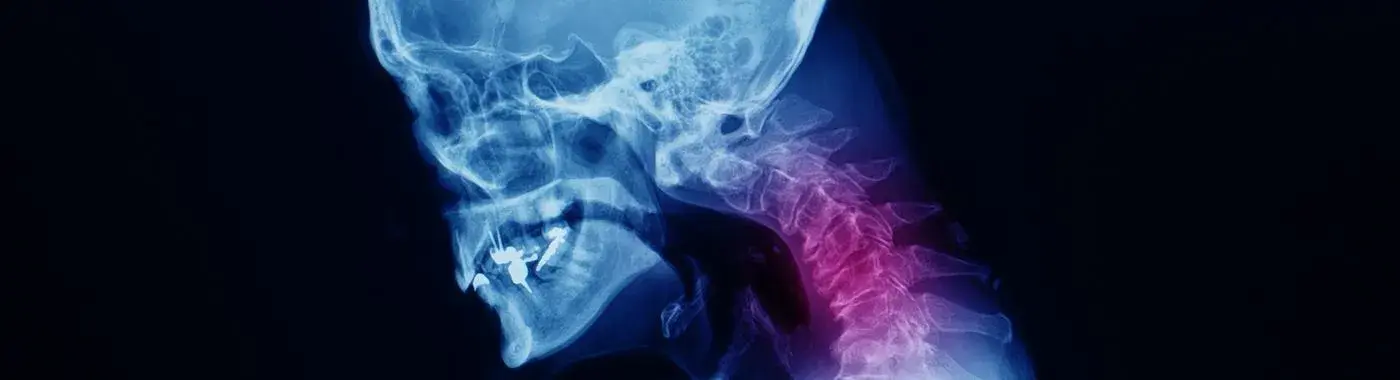

Cervical Spondylosis - Causes, Symptoms, Diagnosis, Treatment, and Prevention

Cervical Spondylosis: Understanding, Managing, and Preventing a Common Condition

Cervical spondylosis is a degenerative condition affecting the cervical spine, which is the portion of the spine located in the neck. As people age, the wear and tear on the spinal discs and joints can lead to this condition, which is often characterized by pain, stiffness, and reduced mobility. Understanding cervical spondylosis is significant not only for those experiencing symptoms but also for the general population, as it highlights the importance of spinal health and proactive management of age-related changes.

Cervical spondylosis is defined as the age-related degeneration of the cervical spine, including the intervertebral discs, vertebrae, and surrounding ligaments. This condition can lead to the formation of bone spurs and the narrowing of the spinal canal, which may compress nearby nerves and result in various symptoms. While it is a common condition, especially in individuals over the age of 40, many people may not experience significant symptoms.

• Imaging Studies: X-rays, MRI, or CT scans are commonly used to visualize the cervical spine and assess the extent of degeneration.